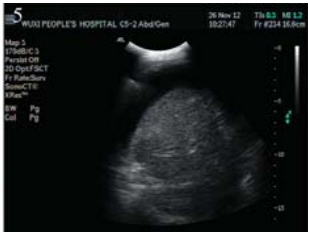

于2012年11月5日在B型超声定位下行肝包膜下 囊性包块穿刺引流,引流液暗红色不凝血,查穿刺 液常规:颜色:暗红色,红细胞计数:150×109/L, 白细胞计数:600×109/L,中性粒细胞70%,淋巴 细胞30%,李凡他试验+,透明度:浑浊。生化: 总蛋白:50.1 g/L,乳酸脱氢酶:1 042 IU/L。肿 瘤指标:CEA:958 ng/ml,CA125:788.2 IU/ml, CA199:>195 9 IU/ml,AFP:5.8ng/ml。脱落细胞 学检查找到癌细胞,见图 4。引流后于2012年11月9 日予顺铂40 mg囊腔内注射,治疗后复查肝脏B型 超声:肝包膜下囊性占位明显缩小,大小约0.8 cm ×0.8 cm,见图 5。

图 5 肝包膜下巨大囊性转移瘤患者B型超声 Figure 5 Abdominal US of huge cystic metastatic tumor of hepatic subcapsular The cystic mass was reduced significantly,the maximum anteroposterior diameter is 8mm×8mm |